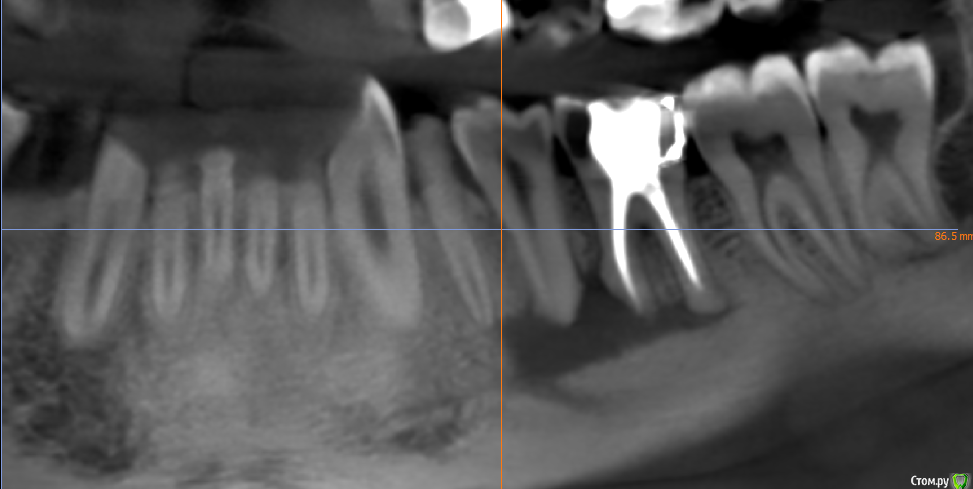

kramer Опубликовано 2 мая, 2018 Поделиться Опубликовано 2 мая, 2018 Коллеги! Помогите, пожалуйста, советом. Пациент обратился с жалобами на зуб 36, характерными для периодонтита (дискомфорт при накусывании, периодические обострения и т.д.). Зубы 35,34 интактные. Сделал КТ, вот что там: Синус-тракт в области 36: Область 35: Мезиально очаг поражения достигает апекса 34 и, видимо, уже частично разрушил компактную пластинку: Если это обычный периодонтит, то 1) почему такие странные очертания очага (или не странные?) 2) с 36 все понятно, но как могли быть поражены 35 и 34? Ссылка на комментарий

TIGER Опубликовано 3 мая, 2018 Поделиться Опубликовано 3 мая, 2018 Коллеги! Помогите, пожалуйста, советом. Пациент обратился с жалобами на зуб 36, характерными для периодонтита (дискомфорт при накусывании, периодические обострения и т.д.). Зубы 35,34 интактные. Сделал КТ, вот что там: раф1.png Синус-тракт в области 36:раф2.png Область 35:раф3.png Мезиально очаг поражения достигает апекса 34 и, видимо, уже частично разрушил компактную пластинку:раф4.png Если это обычный периодонтит, то 1) почему такие странные очертания очага (или не странные?) 2) с 36 все понятно, но как могли быть поражены 35 и 34? Гранулирующий периодонтит от 6 зуба.... Ссылка на комментарий